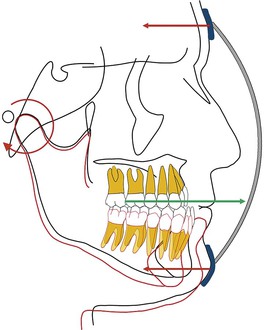

Keles et al.34 studied the effects of varying the force direction on maxillary orthopedic protraction in two groups of patients. The first group received protraction headgear with a force applied by intraoral elastics and the second group received a force applied with a modified protraction headgear as described above.9 The authors reported that in the first group the maxilla rotated counterclockwise (Fig. 16-10), resulting in downward and backward rotation of the mandible, while in the second group an anterior translation of the maxilla with no to minimal mandibular rotation occurred. This important study showed that predictable changes can be achieved in the direction of maxillary advancement with desired or without undesirable mandibular changes.

Figure 16-10 Force diagram of a protraction headgear device using intraoral elastics to deliver force. Note the clockwise moment on the midface and dentition resulting in a downward and backward rotation of the mandible.

By changing the point of force attachment on the facemask or outer bow of the headgear, the vertical dimension of the face can be very nicely controlled. This is especially important in Class III patients with a long vertical dimension and a steep mandibular plane. Similarly, in Class III patients with a flat mandibular plane and a deep bite, a force below the level of the occlusal plane may be more desirable to rotate the mandible downward and backward (see Fig. 16-10). A line of force closer to the center of resistance of the midface will deliver a translatory force (Fig. 16-11) and a line of force closer to the occlusal plane has a rotational force (Fig. 16-12).